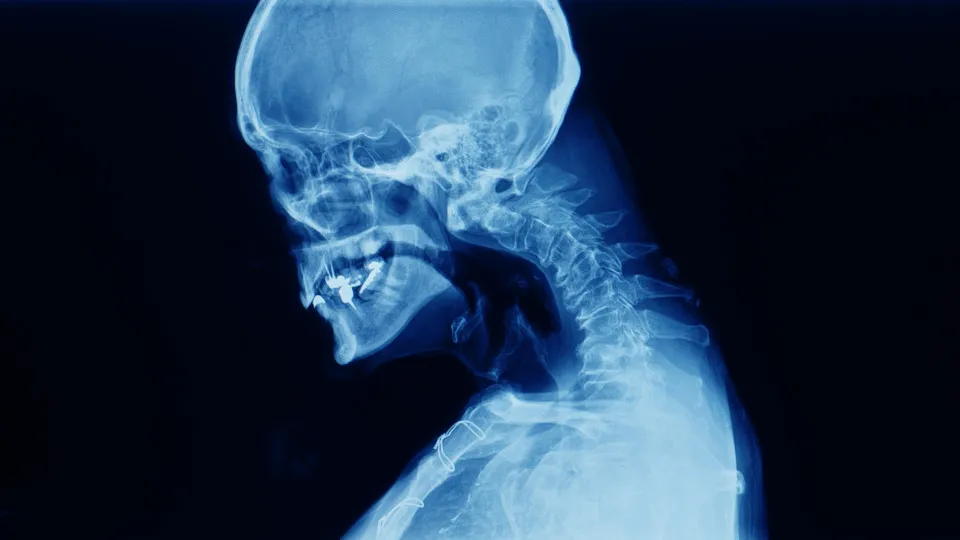

A cifose, isto é, a curvatura excessiva da zona superior da coluna não afeta só idosos. Segundo o ortopedista Ricardo Rodrigues Pinto, da rede de saúde CUF, "na verdade, a cifose surge mais frequentemente durante a adolescência", uma vez que esta é "uma fase em que os ossos crescem mais rapidamente"

Ainda assim, também pode desenvolver-se em adultos mais velhos. "Com o avançar da idade, as vértebras tendem a perder alguma da sua flexibilidade", explica. Por outro lado, "ocorrem frequentemente fraturas osteoporóticas das vértebras da coluna dorsal e dorso-lombar".

"Essas fraturas levam ao acunhamento progressivo das vértebras, tornando-se a coluna progressivamente mais cifótica. Como resultado, a coluna vertebral começa a inclinar-se para a frente", remata.